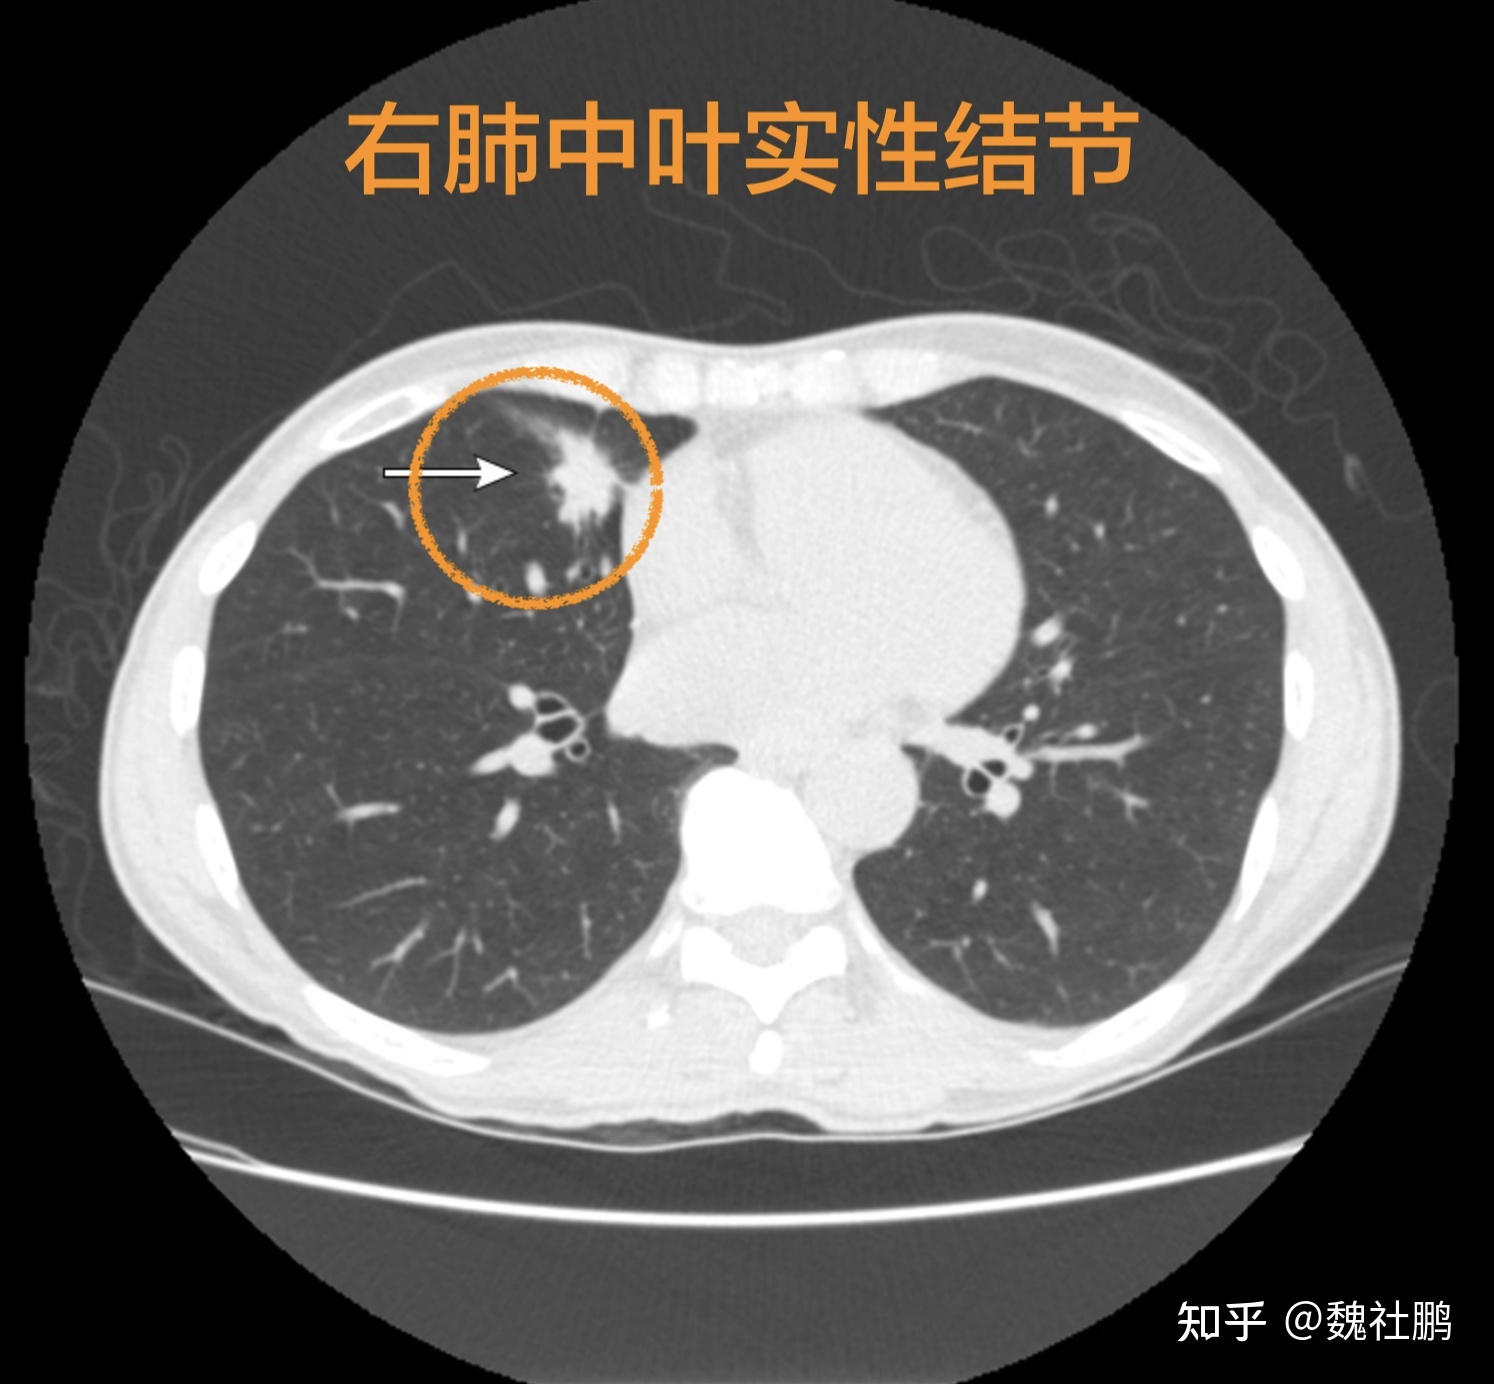

肺结节是指肺内直径小于或等于3cm的类圆形或不规则形病灶,影像学表现为密度增高的阴影,边界清晰或不清晰的病灶。